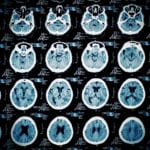

Unlike broken bones or lacerations, minor TBIs don’t appear on standard imaging tests, such as X-rays. The CDC (Centers for Disease Control and Prevention) reports that close to 1.5 million Americans sustain a TBI each year, with motor vehicle accidents being one of the leading causes.